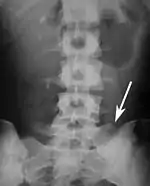

Sacralization of the fifth lumbar vertebra (or sacralization) is a congenital anomaly, in which the transverse process of the last lumbar vertebra (L5) fuses to the sacrum on one side or both, or to ilium, or both. These anomalies are observed in about 3.5 percent of people, and it is usually bilateral but can be unilateral or incomplete (ipsilateral or contralateral rudimentary facets) as well. Although sacralization may be a cause of low back pain, it is asymptomatic in many cases (especially bilateral type). Low back pain in these cases most likely occurs due to biomechanics. In sacralization, the L5-S1 intervertebral disc may be thin and narrow. This abnormality is found by X-ray.

Sacralization of L6 means L6 attaches to S1 via a rudimentary joint. This L6-S1 joint creates additional motion, increasing the potential for motion-related stress and lower back pain/conditions. This condition can usually be treated without surgery, injecting steroid medication at the pseudoarticulation instead. Additionally, if L6 fuses to another vertebra this is increasingly likely to cause lower back pain. [3] The presence of a sixth vertebra in the space where five vertebrae normally reside also decreases the flexibility of the spine and increases the likelihood of injury. [4]